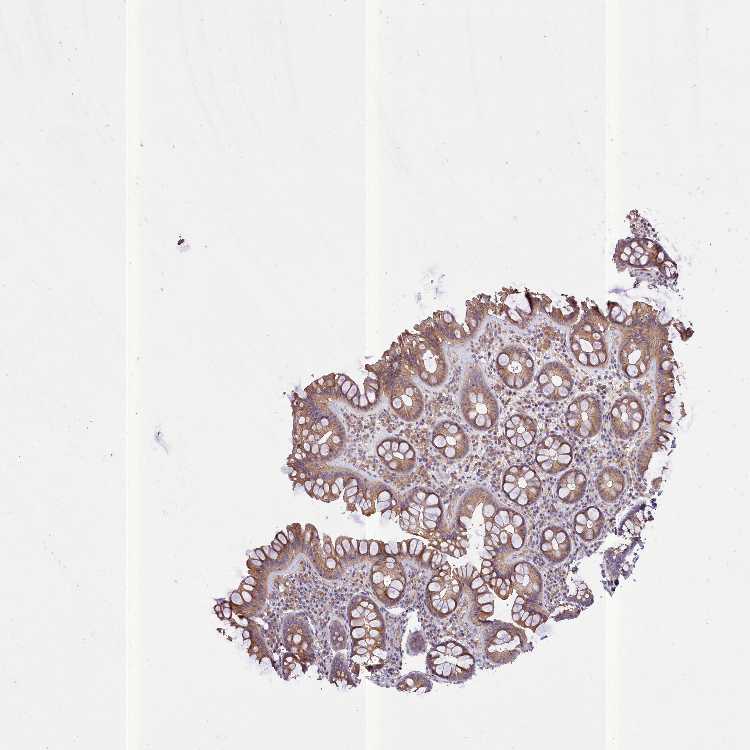

PEMT